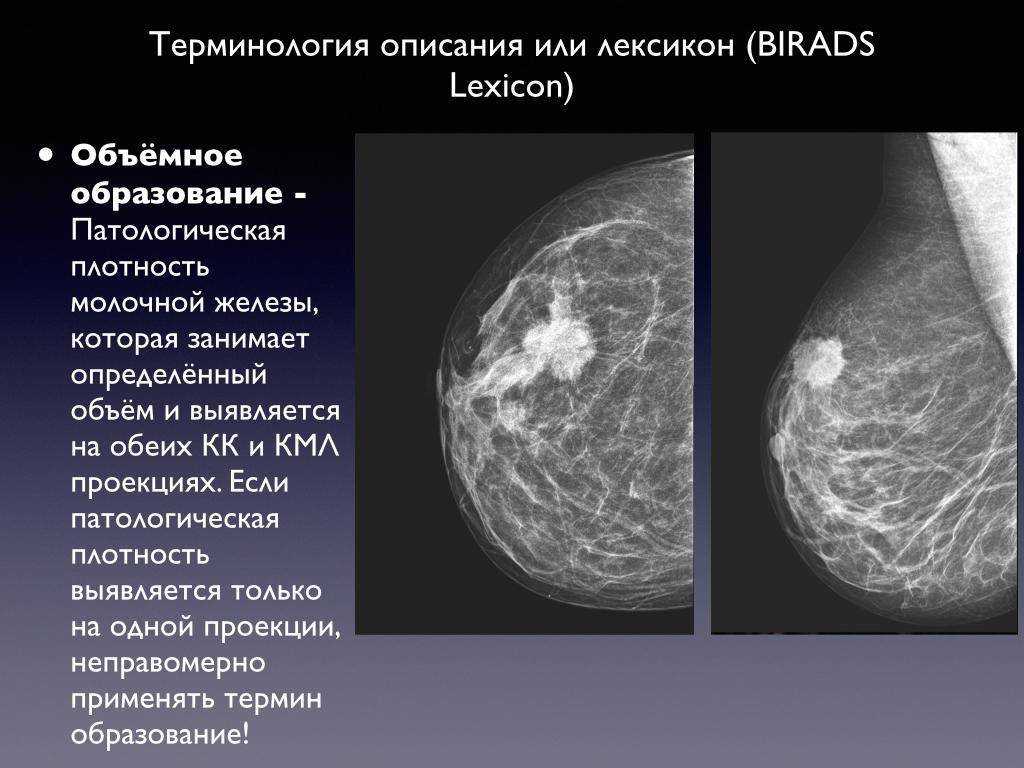

Аномалии молочной железы: медицинские примеры и визуализация

Раздел: Мудрость в деталях